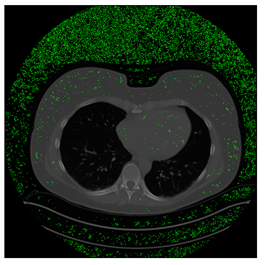

Figure 12.

Sampled images in the tested benchmark databases: (a) Breast-MRI-NACT-Pilot (breast), (b) ACRIN-DSC-MR-Brain (brain), (c) NIH (chest), (d) Lung-PET-CT-Dx (lung), (e) Prostate-MRI (prostate), and (f) Other grayscale standard images.

- Lung-PET-CT-Dx Database (available at: https://wiki.cancerimagingarchive.net/pages/viewpage.action?pageId=70224216 (accessed on 4 November 2021))

Lung-PET-CT-Dx is a CT-type image database collecting lung medical images. Some samples are shown in Figure 12d.

4.3. The Results

In this subsection, we describe three experiments used to measure the performance of the proposed method. The first experiment shows the stegoimage and marks the pixels’ positions that have been modified during the embedding process, as shown in Table 2, Table 3, Table 4, Table 5, Table 6 and Table 7. To make modified pixel positions have a pronounced effect, we set bpp (bit per pixel) rate at 0.05 and 0.025. It can be seen from the results that the proposed local complexity function can distinguish ROI and RONI from most of the medical images, so modified pixels are mainly gathered in RONI. However, it is observed that the proposed local complexity function cannot distinguish between ROI and RONI in the Prostate-MRI database due to the relative complexity of the image. Besides, “Modified BPP” represents the proportion of pixels in the image that have been modified. We observed that the performance of “baboon” in the grayscale standard images database is poor because that image’s pixels are relatively complex. It becomes challenging to select the more embeddable pixels based on the proposed local complexity function. Nevertheless, the modified pixel positions in other grayscale standard images, such as Lena and Barbara, are relatively smooth, verifying that our local complexity function is also applicable to general images.